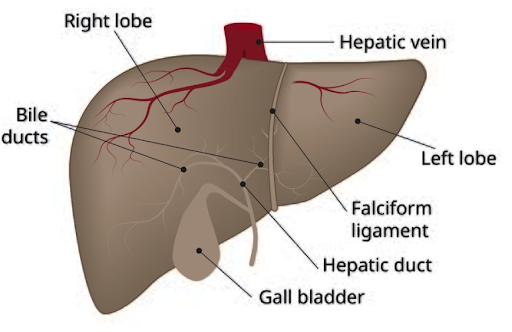

Hepatocellular Carcinoma- Liver cancer

Overview of Liver Cancer

Liver cancer is a condition in which abnormal cells begin to grow in the liver, an organ that plays a vital role in digestion, metabolism, detoxification, and energy storage. Because the liver supports many essential body functions, changes in its health can have a wide impact. Liver cancer often develops gradually and may not cause noticeable symptoms in its early stages, making awareness and timely medical evaluation important.

Liver cancer can affect people of different ages and backgrounds, often influenced by underlying liver health, medical conditions, and certain lifestyle factors. A diagnosis can raise many questions and concerns for both patients and their families, highlighting the importance of clear information, regular follow-up, and supportive care throughout the journey.

Liver cancer is a condition in which abnormal cells begin to grow in the liver, an organ that plays a vital role in digestion, metabolism, detoxification, and energy storage. Because the liver supports many essential body functions, changes in its health can have a wide impact. Liver cancer often develops gradually and may not cause noticeable symptoms in its early stages, making awareness and timely medical evaluation important.

Liver cancer can affect people of different ages and backgrounds, often influenced by underlying liver health, medical conditions, and certain lifestyle factors. A diagnosis can raise many questions and concerns for both patients and their families, highlighting the importance of clear information, regular follow-up, and supportive care throughout the journey.

Where Liver Cancer Begins

Hepatocellular carcinoma originates in the liver, a large organ situated in the upper right quadrant of the abdomen. The liver is responsible for processing nutrients, producing bile, regulating blood clotting, and removing toxins from the body.

Who is commonly diagnosed?

Hepatocellular carcinoma may be seen in:

- Adults, more commonly over the age of 40

- Men more often than women

- Individuals with long-standing liver conditions

- Populations with higher rates of viral hepatitis

How does Liver cancer usually develop?

HCC typically develops over time as healthy liver cells undergo gradual changes due to chronic inflammation or repeated injury. These altered cells may begin to grow uncontrollably, forming a tumor. In many cases, this process occurs in a liver already affected by scarring (cirrhosis) or long-term liver disease.

Possible Risk Factors

Several factors may increase the likelihood of developing hepatocellular carcinoma, including:

- Chronic hepatitis B or hepatitis C infection

- Liver cirrhosis from any cause

- Long-term alcohol consumption

- Fatty liver disease is linked to obesity or diabetes

- Exposure to certain toxins (such as aflatoxins)

- Genetic or inherited liver disorders